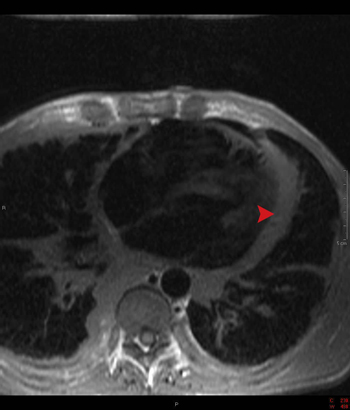

This axial spin echo image shows a pericardium that is thicker than the normal 3 mm (arrowhead). This finding is consistent with constrictive pericarditis, but clinical correlation is necessary to determine if the patient is symptomatic.